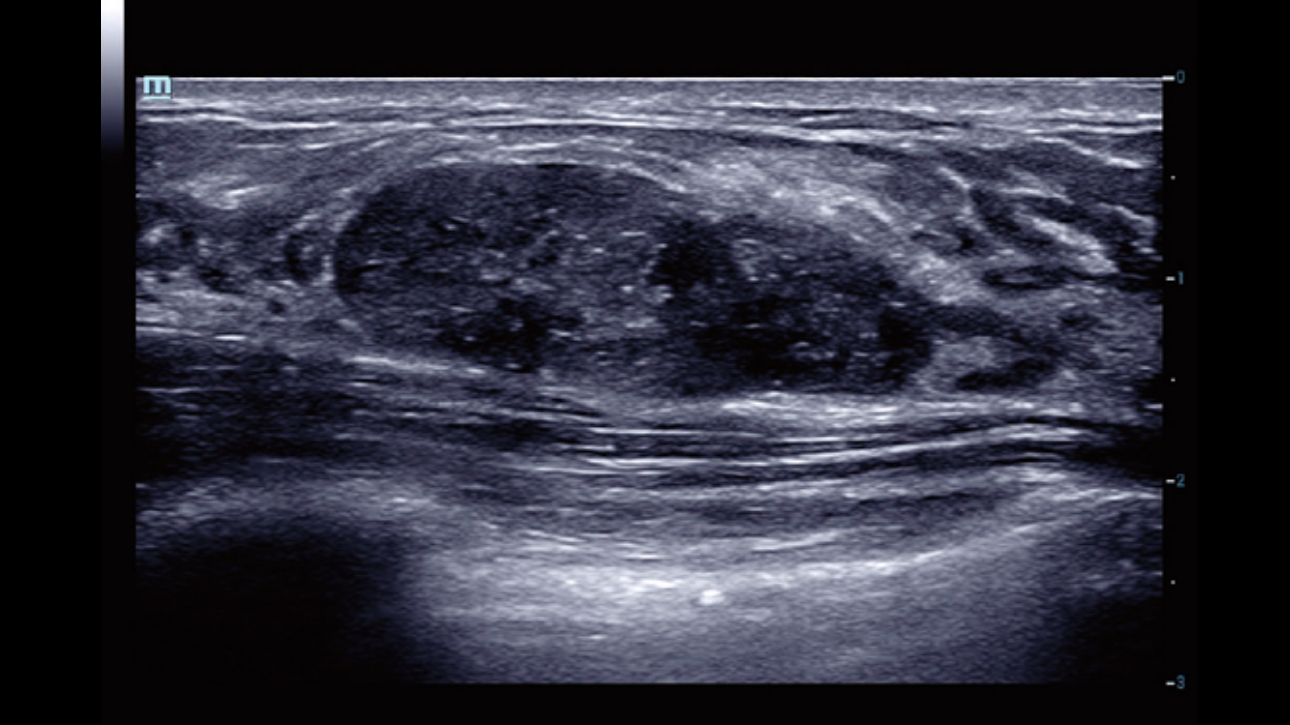

Dynamic Pixel Focusing technology allows the Resona 6 to achieve extreme uniformity in pixel level throughout the whole field of view. Now there's no need to adjust the focal positions to achieve uniformity across patient exams.